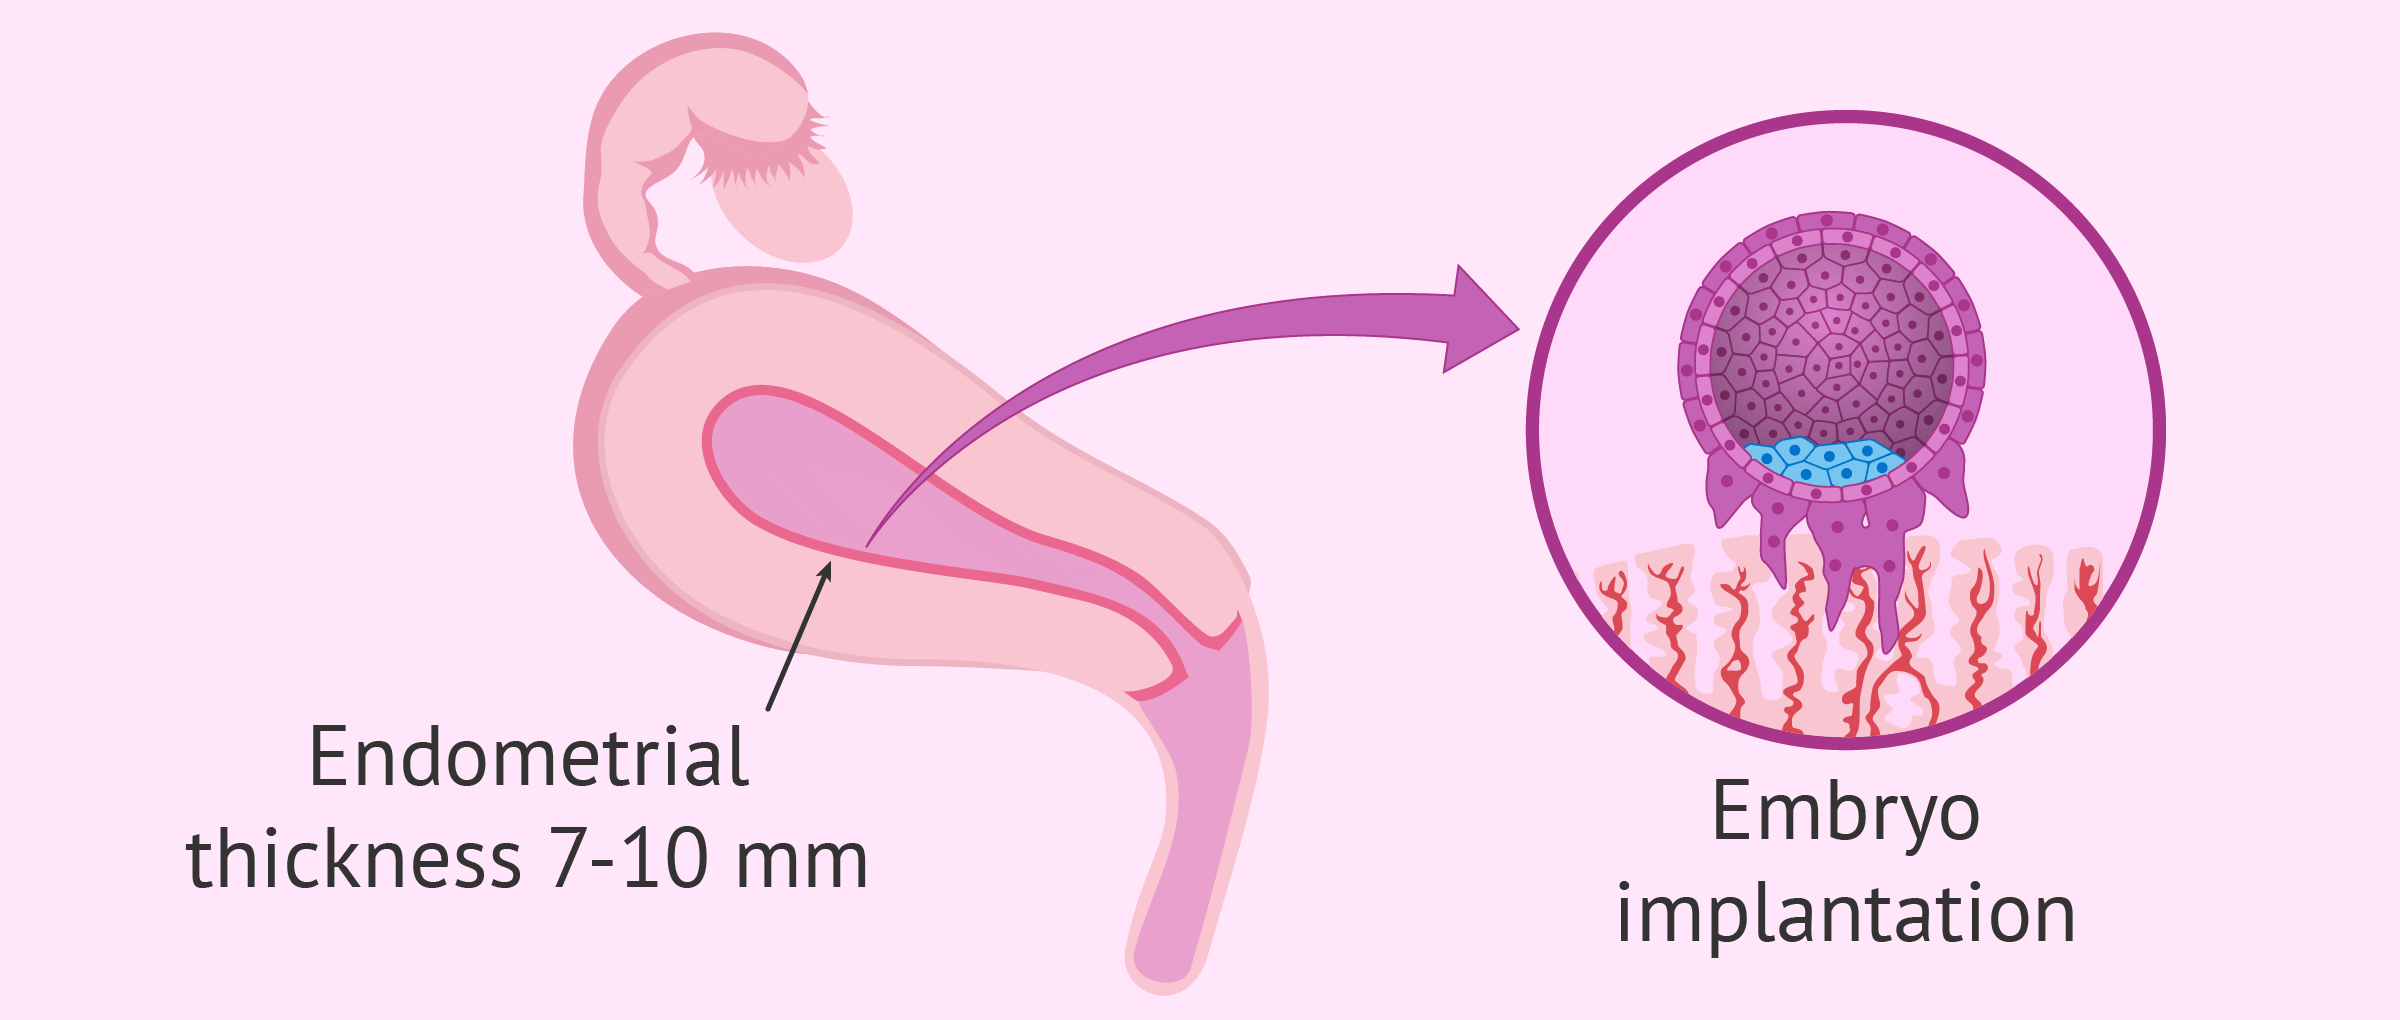

Endometrial Thickness Whats The Normal Range For Conceiving .

Endometrial Thickness What Is The Normal Range .

Endometrial Thickness Whats The Normal Range For Conceiving .

Endometrial Thickness Whats The Normal Range For Conceiving .

6 Effective Ways To Increase Endometrial Thickness Naturally .

How To Improve Your Uterine Lining To Prepare For Ivf .

Endometrial Thickness Whats The Normal Range For Conceiving .